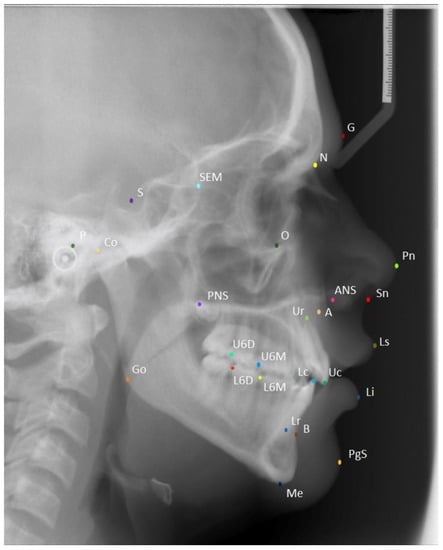

| Landmark | Description |

|---|---|

| S (Sella) | The geometric center point of the pituitary fossa. |

| P (Porion) | The most superior point on the external auditory meatus. |

| Go (Gonion) | Most posterior and inferior point on the curvature of the angle of the mandible. |

| N (Nasion) | The most anterior point on the frontonasal suture. |

| O (Orbitale) | The lowest point on the inferior rim of the orbit. |

| A (Point A) | The deepest point on the bony concavity between the ANS and supradentale. |

| B (Point b) | The deepest point on the bony concavity between the pogonion and infradentale. |

| Me (Menton) | The most inferior point on the hard tissue chin. |

| G (Glabella) | The most anterior point on the forehead. |

| Sn (Subnasale) | The junction of the nose and upper lip. |

| Ls (Labrale superius) | The most prominent point on the upper lip. |

| Li (Labrale inferius) | The most prominent point on the lower lip. |

| PgS (Soft tissue pogonion) | The most prominent point on the soft tissue chin. |

| Ur | The root tip of the upper incisor. |

| Uc | The crown tip of the upper incisor. |

| Lc | The crown tip of the lower incisor. |

| Lr | The root tip of the lower incisor. |

| ANS (Anterior nasal spine) | Anterior tip of the nasal spine. |

| PNS (Posterior nasal spine) | Posterior tip of the nasal spine. |

| U6M Upper first molar mesial tip | Most prominent point on the mesial cusp. |

| U6D Upper first molar distal tip | Most prominent point on the distal cusp. |

| L6M Lower first molar mesial tip | Most prominent point on the mesial cusp. |

| L6D Lower first molar distal tip | Most prominent point on the distal cusp. |

| SEM (Sphenoethmoidal point) | Intersection of the greater wing of sphenoid and the cranial floor. |

| Pn (Pronasale) | The most anterior point on the nose. |

| Co (Condylion) | The most superior and posterior point on the condylar head. |